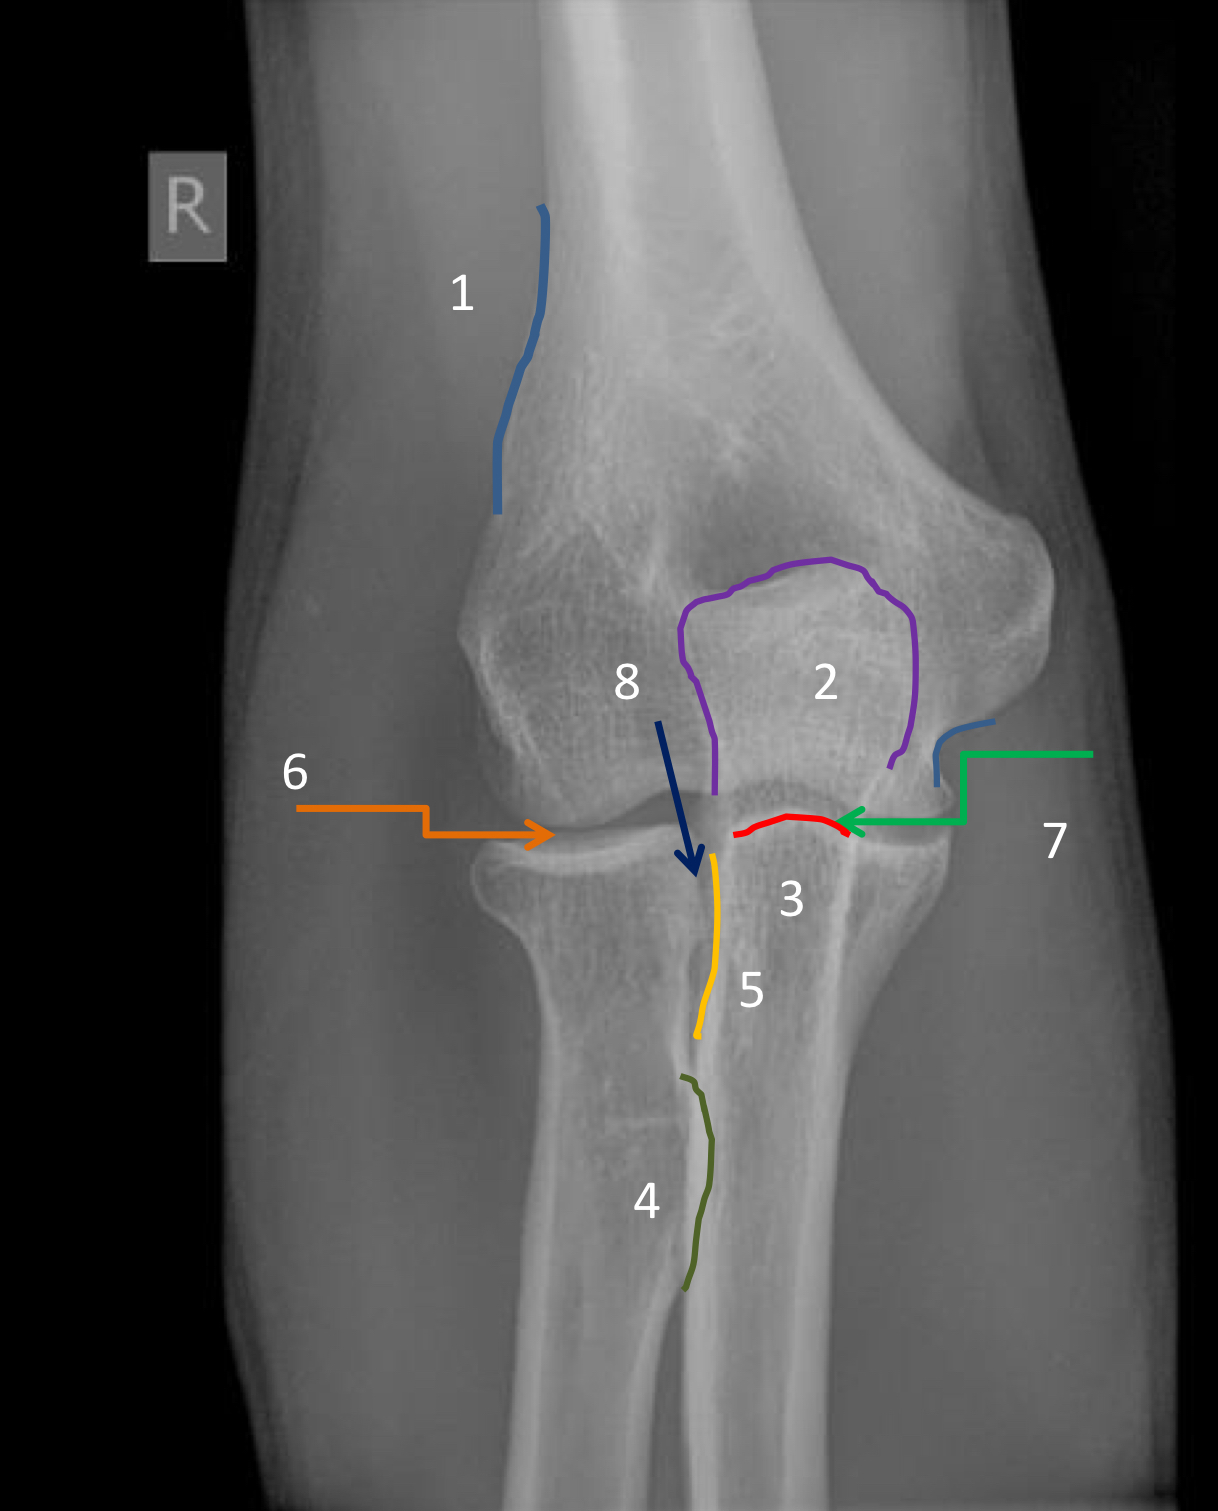

1?

medial epicondyle

2?

medial supracondylar ridge

3?

lateral epicondyle

4?

lateral supracondylar ridge

5?

radial head

6?

capitellum

7?

trochlea

8?

anterior trochlear notch including coronoid process

9?

neck of radius

10?

radial tuberosity

11?

olecranon foassa (and superimposed coronoid process)